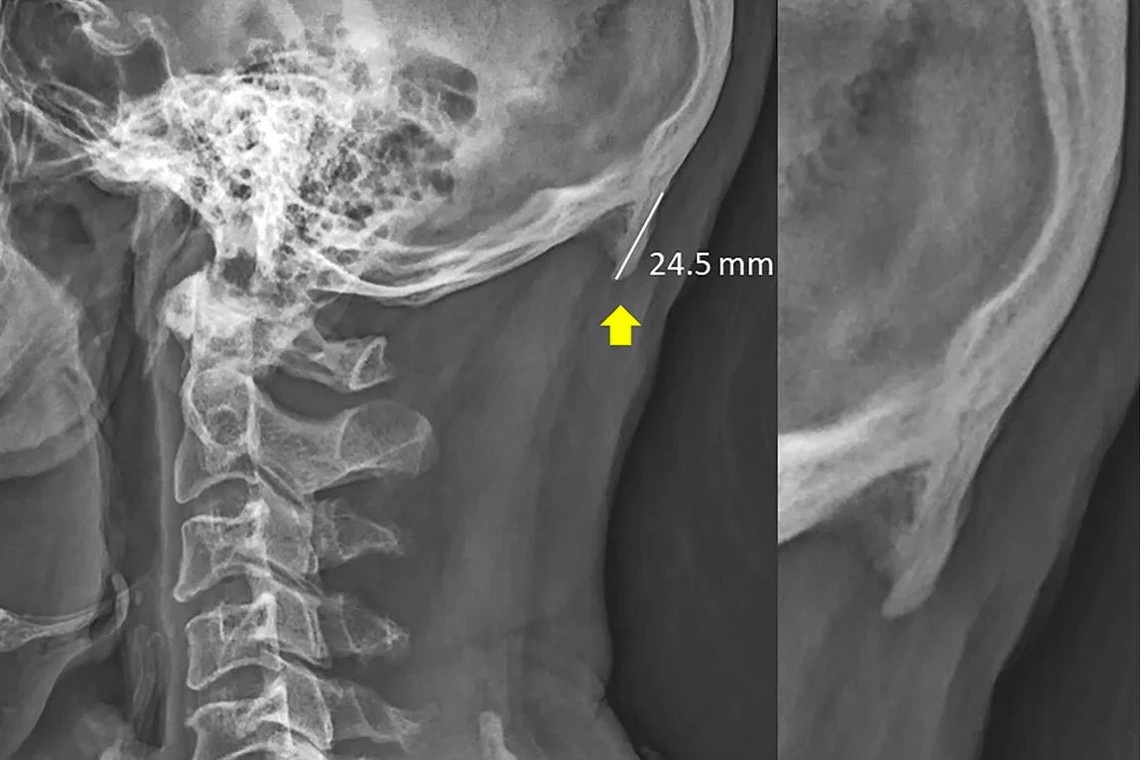

Учёные пришли к выводу, что человек, который постоянно наклоняется над смартфоном, может столкнуться с проблемой: от одной и той же позы над шеей появляется нарост в виде костной выпуклости.

Исследования показали, что треть населения имеет изменения костных тканей. Более того, с такой проблемой начало сталкиваться более молодое население, чем прежде.

Учёный объяснил, что причиной тому служит поза, в которой человек находится, а именно наклоняется к своему планшету или смартфону. К сожалению, современные технологии заполонили нашу жизнь, и очень сложно решить проблему, т.к. отказаться от них просто невозмозжно.